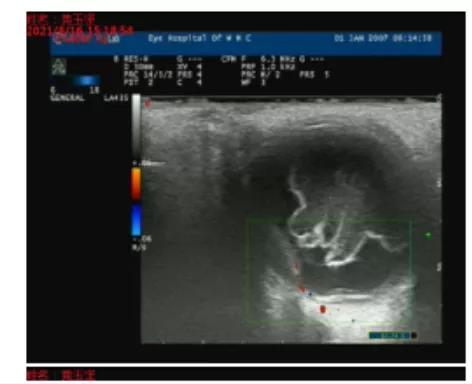

圖 | 術(shù)前彩超

? ? ? 黃爺爺家屬們最終尋求魏勇主任的幫助。魏勇主任初步判斷黃爺爺可能患了一種特殊的黃斑疾病(右眼息肉狀脈絡(luò)膜血管病變,簡(jiǎn)稱“PCV”)導(dǎo)致視網(wǎng)膜下大量出血,這種出血會(huì)讓患者視力急劇下降,如不及時(shí)治療,短時(shí)間就會(huì)導(dǎo)致患眼永久失明。目前黃爺爺患眼已經(jīng)無(wú)光感,是否能將視力搶回來(lái),一切都是未知數(shù)。雖然這項(xiàng)手術(shù)在魏勇團(tuán)隊(duì)已經(jīng)開(kāi)展多年,但之前的手術(shù)大多針對(duì)有光感的患者,極少數(shù)術(shù)前無(wú)光但眼壓極高的患者才給予手術(shù)治療。

? ? ? 考慮到黃爺爺患眼無(wú)光感的時(shí)間短,同時(shí)擔(dān)心黃爺爺進(jìn)一步出血可能導(dǎo)致眼壓急劇升高不得不手術(shù),而那時(shí)候手術(shù),恢復(fù)視力的可能性極低。在患者和家屬?gòu)?qiáng)烈的手術(shù)愿望及充分的信任下,魏勇主任及其團(tuán)隊(duì)決定盡全力手術(shù),抓住最后恢復(fù)視力的機(jī)會(huì)。